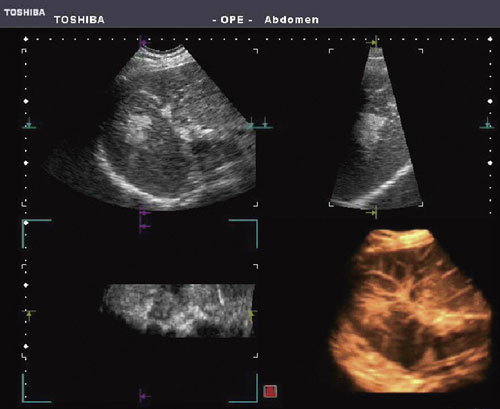

4D-CHI(Contrast Harmonic Imaging)は,腹部領域において広く行われている造影エコーを4D Imagingと組み合わせた機能である。

従来の2D像での造影エコーでは,1回の造影剤投与で染影の時間的変化が観察できる領域は限られていたが,4D-CHIでは染影画像をボリュームデータとして収集するので,例えば,肝腫瘍に対するRFA後の染影画像をMulti Viewで観察すると,腫瘍の隅々にわたって治療効果確認を行うことができる。もちろん,染影画像を4D像としてリアルタイム表示することができるので,血流の走行状態や血管の形態的な異常といった診断情報をより客観的に伝えることが可能となる(図4)。

また,2D-CHIで好評のMFIモードにも対応しており,造影剤によって得られた染影の高輝度情報を重畳表示することで,より細かな管腔構造を滑らかに描出することもできる。

図4 4D-CHIによる肝腫瘍の染影像

(画像ご提供:東京医科大学・森安史典先生) |